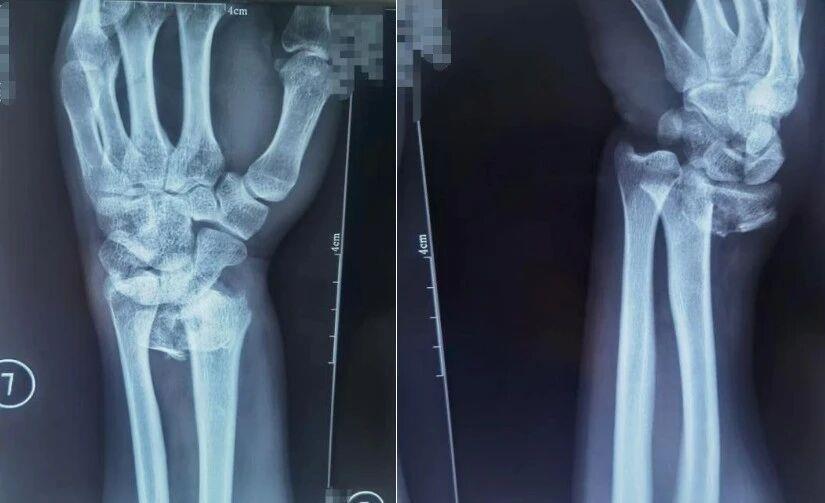

跌倒時用手腕撐地是常見的自我保護動作,但這一動作極易導致橈骨遠端骨折,表現為手腕腫脹疼痛、活動障礙,嚴重時還會出現明顯畸形。

△患者橈骨遠端骨折,圖為復位前正位、復位前側位。圖源:哈爾濱骨傷科醫院